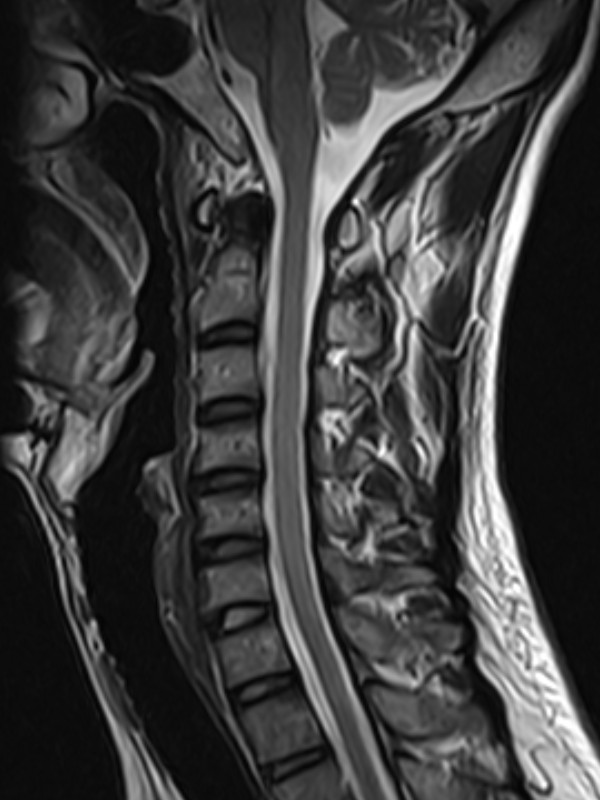

颈椎-T2

1524110738182785.jpg